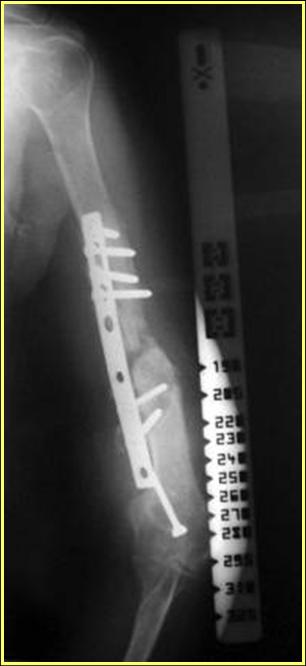

Типичная положительная ситуация для интрамедуллярного остеосинтеза с

использованием опорного металлокаркаса для компенсации дефекта.

Послеоперационное ведение активное или агрессивно-активное. Каркасы

можно заказать в МАТИ.

Рентгеновская версия реконструкции. хронология:

после операции, 2 мес. после операции, через 1 год

Движения в полном объеме восстановлены к 2 мес. после операции. Если надо могу показать мультик. Сейчас уже прошло более 3 лет, больная не

показывается. Успехов ЛАФ.